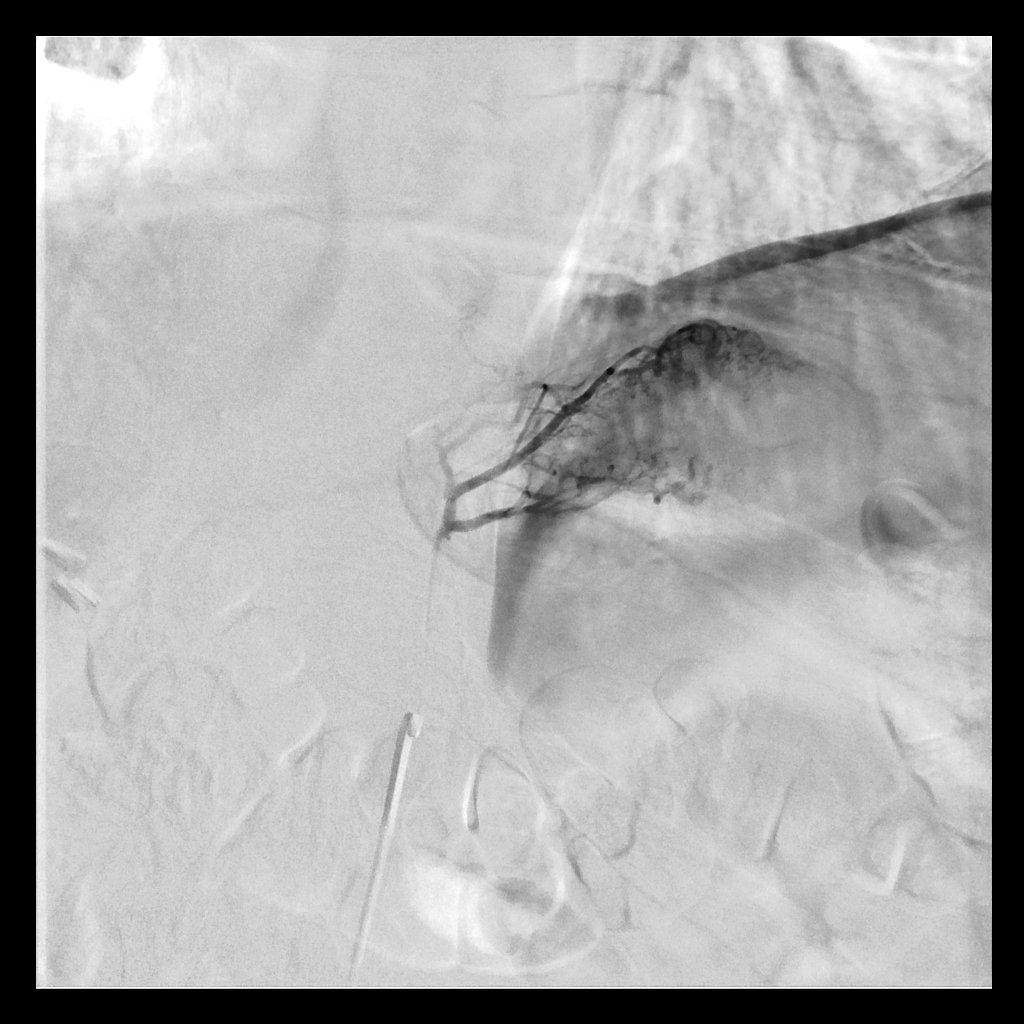

SubM PE. Post CDT refractory hypoxia, indigo aspirated RLL occlusion. Way better, although mPAP no change, others seen this often?